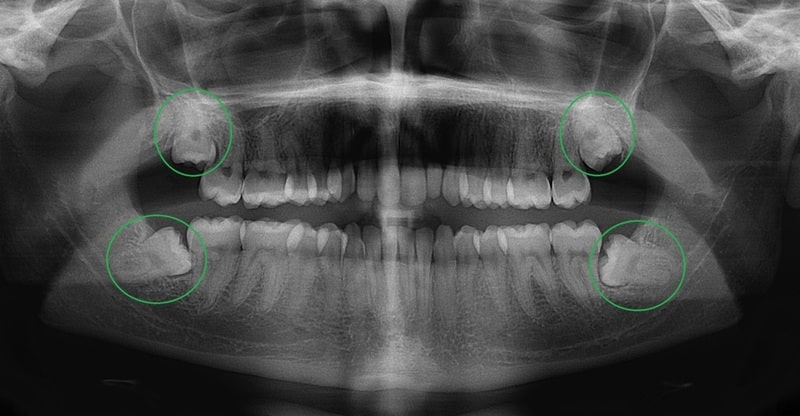

Hình ảnh răng khôn mọc lệch

Trường hợp răng khôn mọc lệch và chèn vào các răng bên cạnh còn có thể gây ảnh hưởng xấu đến các răng bên cạnh và là nguyên nhân gây ra các biến chứng như viêm lợi trùm, viêm túi lợi có mủ, viêm nướu, nhiễm trùng,… Điều này không chỉ khiến người bệnh đau nhức mà còn có thể bị sốt. Vì thế, ngay khi thấy những cơn đau răng đầu tiên, người bệnh cần đến thăm khám tại các cơ sở nha khoa để được kiểm tra và tiến hành nhổ bỏ răng khôn theo chỉ định của bác sĩ để đảm bảo sức khỏe răng miệng và sức khỏe cơ thể.

Hình ảnh chụp X-quang bệnh nhân mọc răng khôn